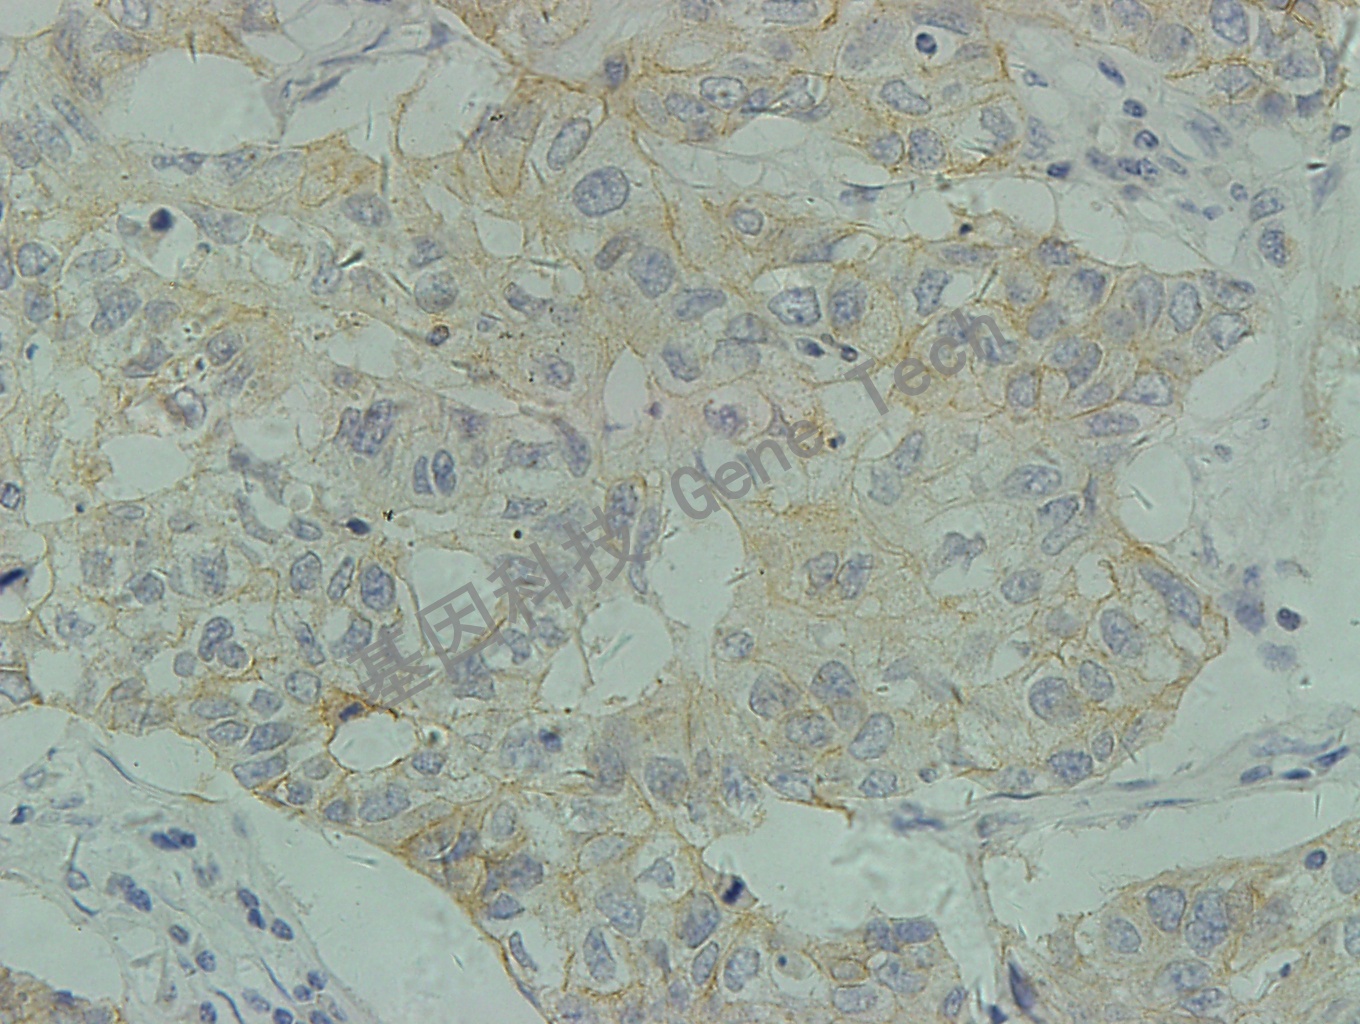

乳腺浸润性导管癌C-erbB-2,1+,≤ 10%的浸润癌细胞呈现不完整的、微弱的细胞膜染色。(10X)

乳腺浸润性导管癌C-erbB-2,1+,≤ 10%的浸润癌细胞呈现不完整的、微弱的细胞膜染色。(40X)